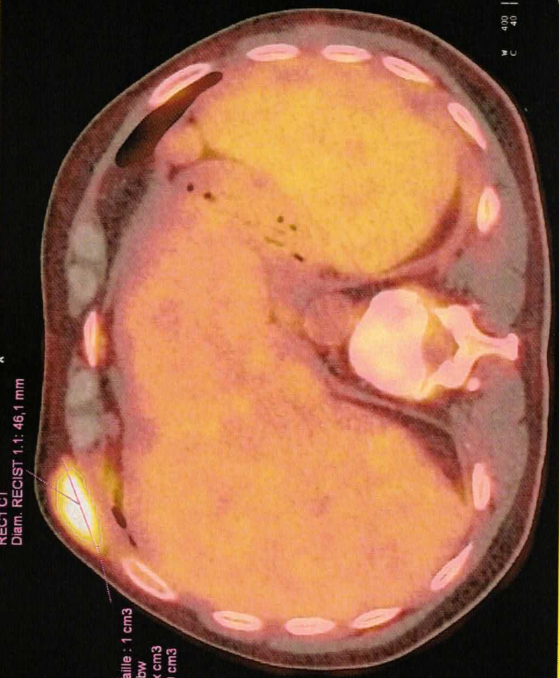

Voici quelques images du TEP Scan:

Plus c’est jaune, plus il y a de cellules cancéreuses qui se régalent en consommant le sucre radio-actif, on voit cette boule jaune au dessus de côtes, mais j’en avais une bonne dizaine à l’intérieur du corps. C’était la zone la plus hyper-métabolique de mon TEP Scan, une boule de 5 cm indolore qui avait poussé en quelques semaines. Mais on voit qu’il y en a aussi dans la rate et le foie …